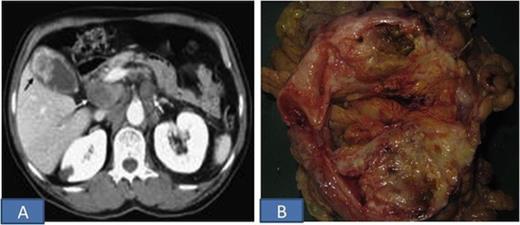

The patient underwent cholecystectomy & wedge resection of the liver with resection of transverse colon and paraduodenal lymph nodes. Intra-operatively, a hard mass in the fundal region of gall bladder, adherent to the transverse colon was seen. Grossly, the tumor measured 7x5x3 cm and was solid grey-white (Figure 1B). The tumor was adherent to the colon but not infiltrating the wall of colon or underlying liver. Microscopic sections showed features of sarcomatoid carcinoma with focal squamous differentiation (Figure 2). The tumor cells were immunopositive for cytokeratin and vimentin. The tumor infiltrated into the adventitia of colon, however muscularis propria and mucosa were free of tumor. The underlying liver parenchyma, resected margins of liver, intestine, cystic duct and eleven lymphnodes dissected from specimen were free of tumor. Paraduodenal lymph nodes were also free of tumor.

A. H&E stained section shows presence of both malignant epithelial (squamous) and mesenchymal (spindle) components (X100); B. Tumor at higher magnification (X200); C. Mesenchymal (spindle) component of tumor (X100)